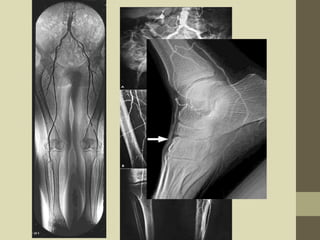

Lower limb angiography

The radiological examination

of the arteries supplying pure

blood to the lower limbs by

the help of seldinger technique

with the retrograde

catheterisation of a femoral

artery.

Filming

• For a bilateral examination, the patient is

positioned in the supine position for single plane

AP projections and the patient is centered to the

midline of the image receptor to include the area

from the aortic bifurcation to the ankles

• Projections

PA if the xray tube is undercouch

AP if xray tube is overhead

lateral